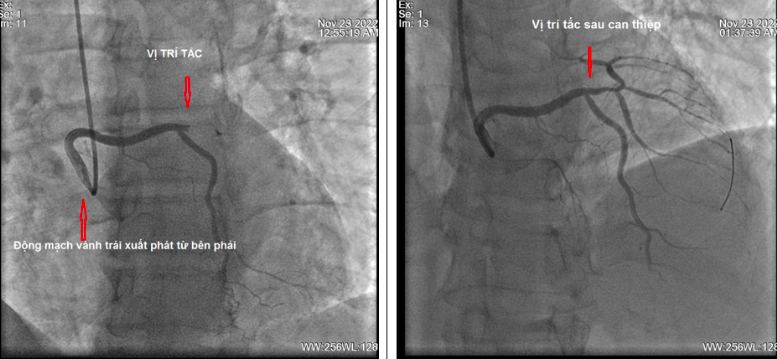

Sau khi được xử trí cấp cứu ban đầu, bệnh nhân được đưa ngay vào phòng can thiệp mạch để chụp và can thiệp tái thông mạch vành bị tắc. Kết quả chụp động mạch vành lại cho thấy bệnh nhân có giải phẫu động mạch vành trái xuất phát rất bất thường.

Động mạch vành trái bị tắc hoàn toàn một nhánh rất lớn, nhưng động mạch này không xuất phát bình thường từ xoang vành trái mà lại xuất phát từ xoang vành phải. Đây là một trường hợp rất hiếm gặp, gây nhiều khó khăn khi chụp và can thiệp động mạch vành. Đó là do các ống thông chụp động mạch vành trái thông thường không thể tiếp cận được lỗ vào của động mạch vành trái.

Kíp kỹ thuật đã hội chẩn và quyết định sử dụng loại ống thông can thiệp dành cho động mạch vành phải, kết hợp với một loại ống thông chuyên dụng nhỏ hơn đi bên trong để tiếp cận động mạch vành trái.

Cuối cùng, sau khi tiếp cận được lỗ vào động mạch vành trái, nong chỗ tắc bằng bóng, các nhánh động mạch vành đều lưu thông máu tốt, bệnh nhân đỡ đau ngực ngay sau thủ thuật.